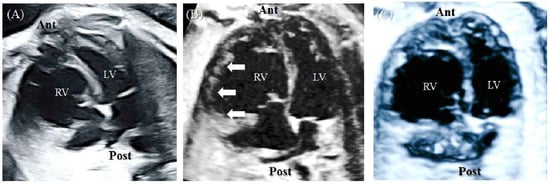

A 43-year-old pregnant woman with dichorionic diamniotic (DCDA) twins was referred due to abnormal fetal ultrasonographic findings for one of the twins. At a gestational age (GA) 26+2 weeks, fetal echocardiography of the upper fetus showed an enlarged and globular right ventricle (RV) with midsystolic tricuspid regurgitation (TR) when compared with the findings for the lower fetus (Figure 1A,B). Except for the ventricular differences and TR, the cardiac structures of the upper fetus were normal, and there were no associated abnormalities. In early pregnancy, the mother underwent genetic amniocentesis because of her advanced age, and the karyotypes of both fetuses were normal. Additionally, the detailed sonographic findings of the lower fetus were normal. At a GA of 30+5 weeks, the globular shape of the RV remained unchanged, but holosystolic TR was observed (Figure 1C,D). Since there was a risk of fetal hydrops or demise due to the progression of TR, Doppler testing, including the ductus venosus, was performed, and the results were normal (Figure 1E).

Figure 1. This is a figure. Schemes follow the same formatting.(A) At 26+2 weeks GA, the upper fetus showed globular RV enlargement compared with (B) the lower fetus, who had a normal heart. (C) At 30+5 weeks GA, the globular shape of the RV remained unchanged, but (D) holosystolic TR was observed. (E) Doppler evaluation of the ductus venosus showed normal findings. Ant, anterior; Lt, left; LV, left ventricle; Post, posterior; Rt, right; RV, right ventricle.